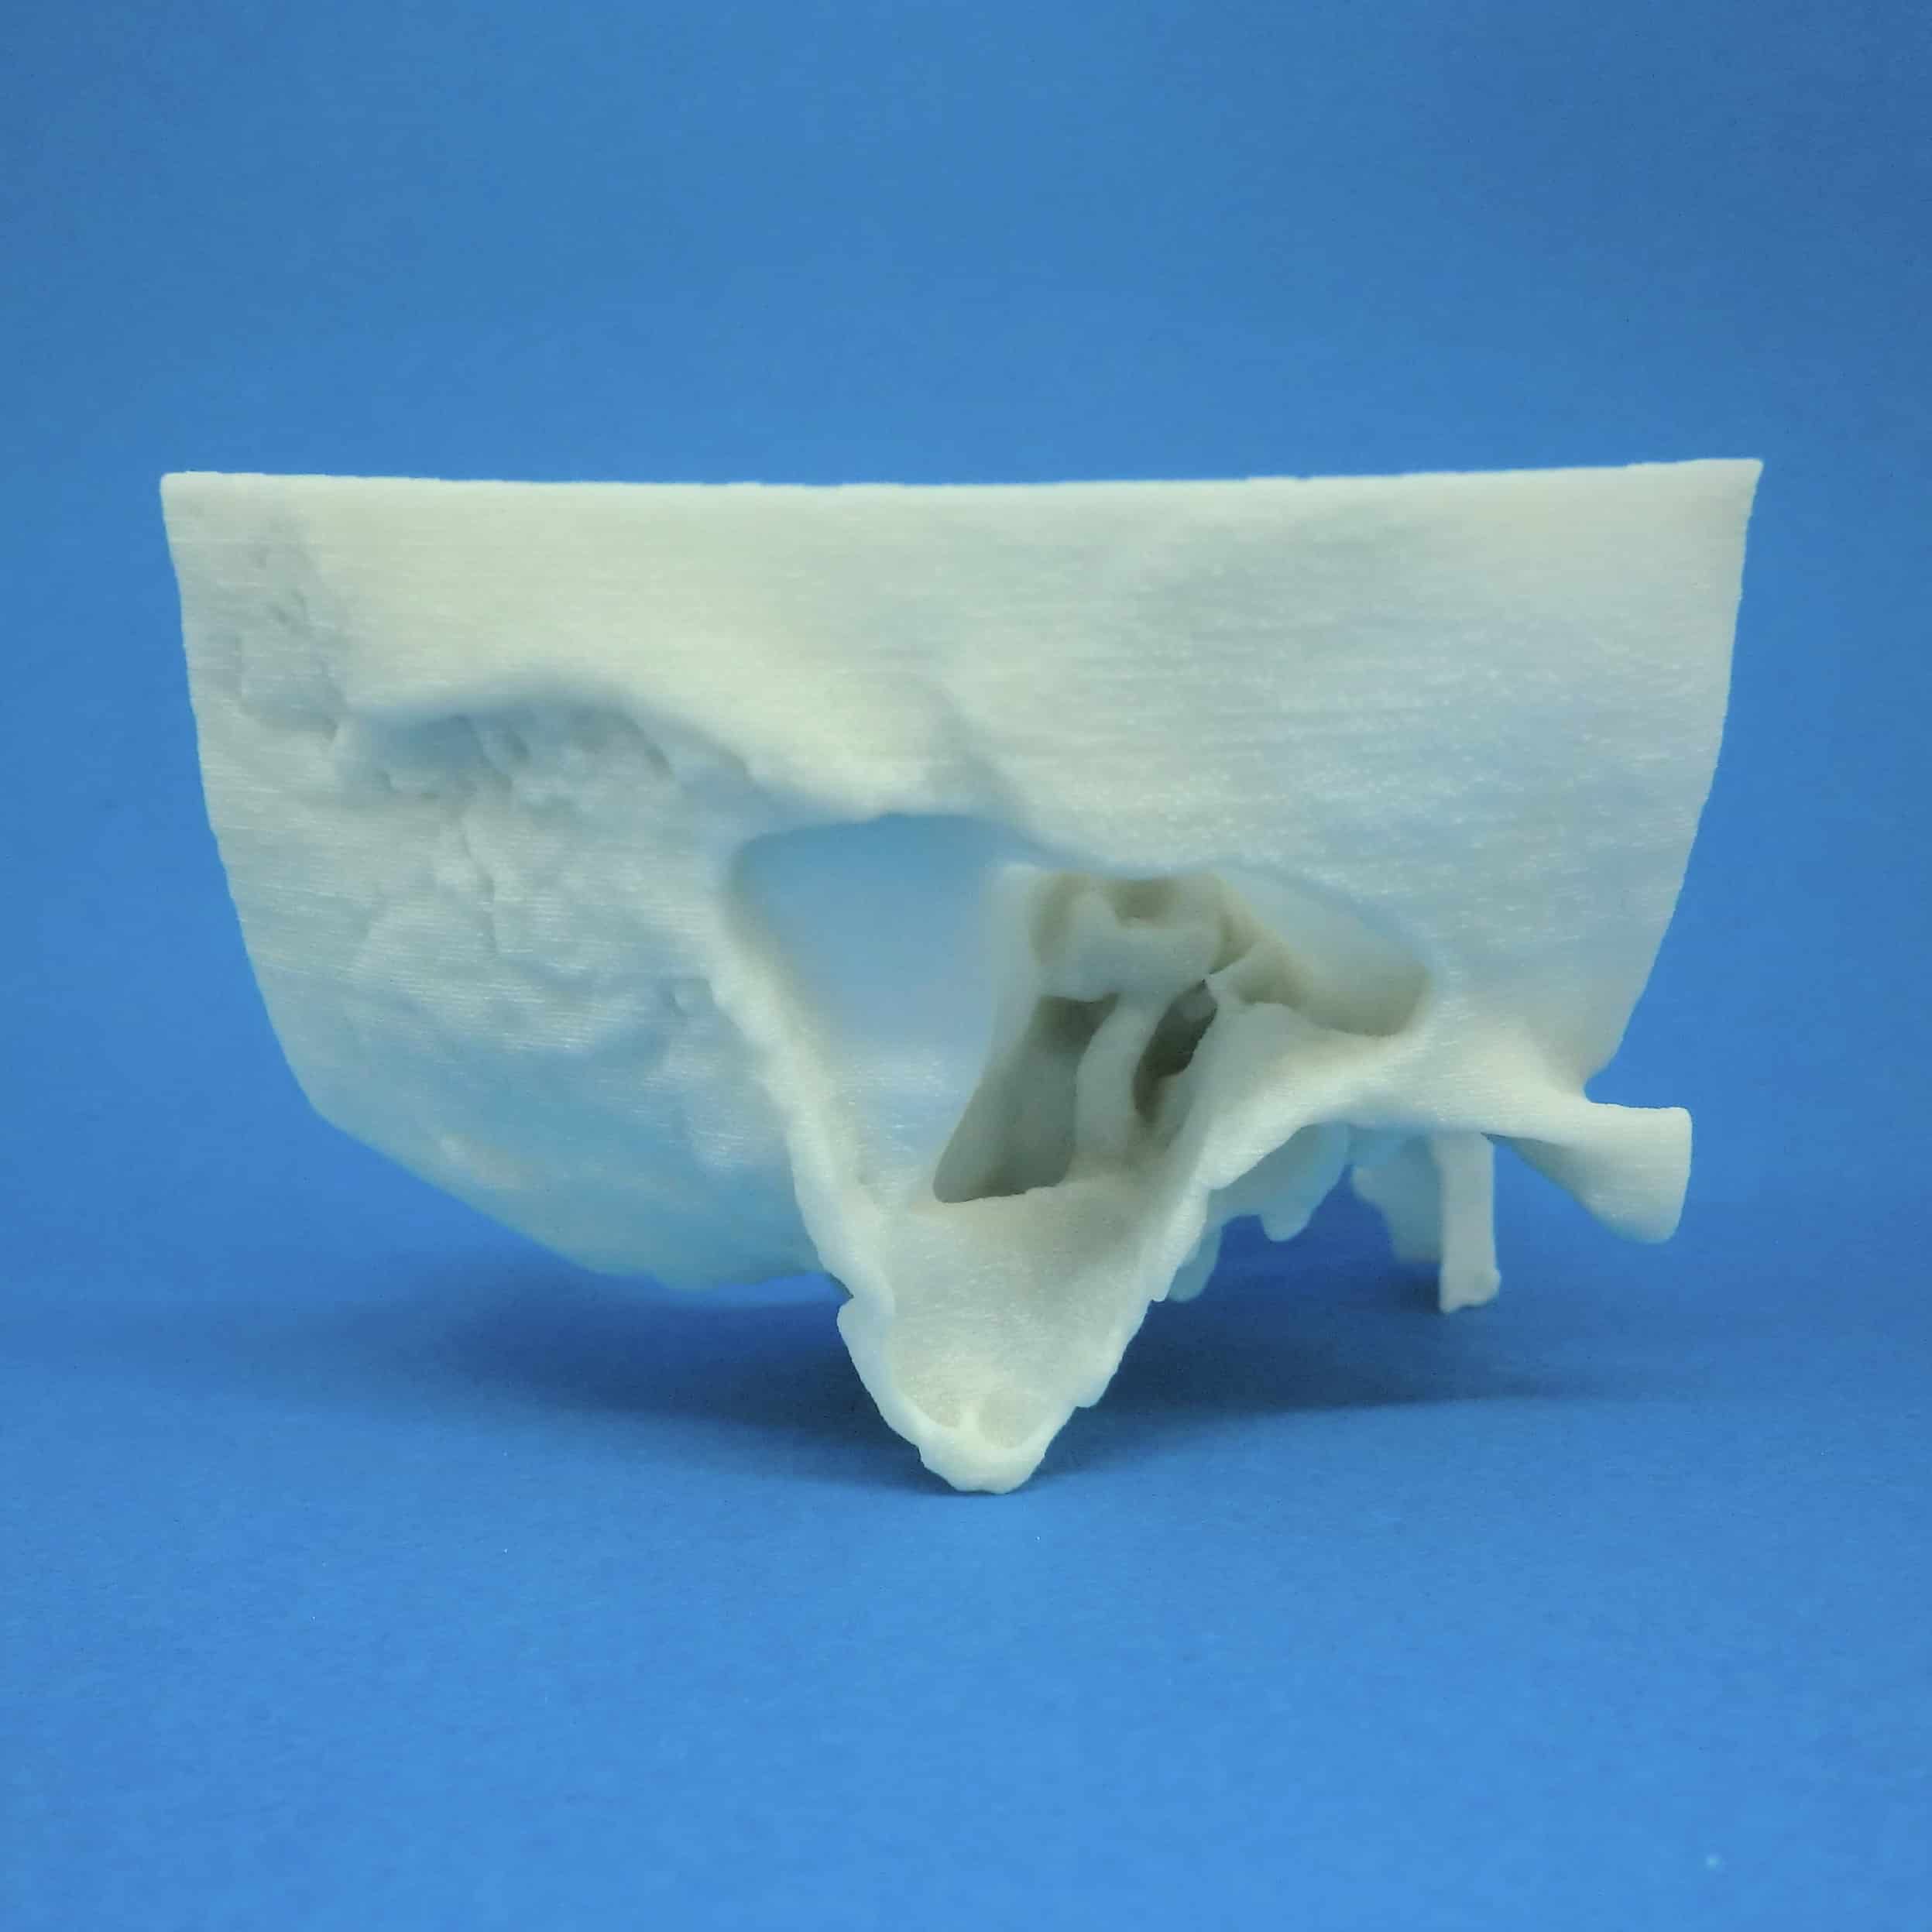

下記に商品説明や配送料・配送方法・注意事項等の説明がございます。Surgical Approaches to the Facial Skeleton | 9780781754996。W側頭骨 削開済 3 C12-3の医療模型 | 3DモデルのKEZLEX。

【インボイス制度対応済み】当社では2023年10月からインボイス制度に対応した適格請求書発行事業者番号(通称:T番号・登録番号)を印字した納品書(明細書)を商品に同梱してお送りしております。こちらをご利用いただくことで、税務申告時や確定申告時に消費税額控除を受けることが可能になります。Search - Endonasal skull base surgery | KARL STORZ Endoskope。CAS: Asymmetry correction for Laterognathia。どちらのサイトからもご購入可能です。